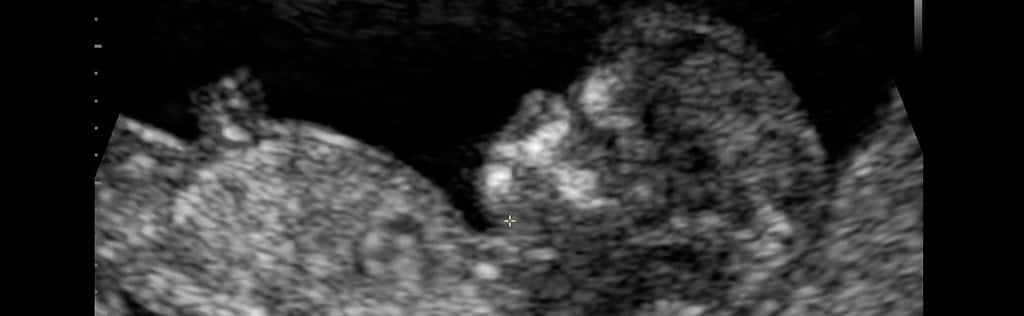

Si effettua tra la 12^ e la 14^ settimana di gravidanza mediante un’ecografia che permette di misurare la Translucenza Nucale (NT, uno spazio presente a livello della nuca del feto che quanto più supera i 2.5 mm più aumenta il rischio della sindrome di Down e di cardiopatie congenite) quando la lunghezza del feto (CRL, lunghezza vertice-sacro) è compresa tra 45 e 87 mm. Si esegue contemporaneamente un prelievo ematico della mamma che ha lo scopo di misurare il livello di 2 sostanze (free-β-hcg e PAPP-A) che un particolare software utilizza per l’elaborazione statistica del rischio. Non è necessario il digiuno prima del prelievo.

L’ecografia viene solitamente effettuata per via trans addominale.